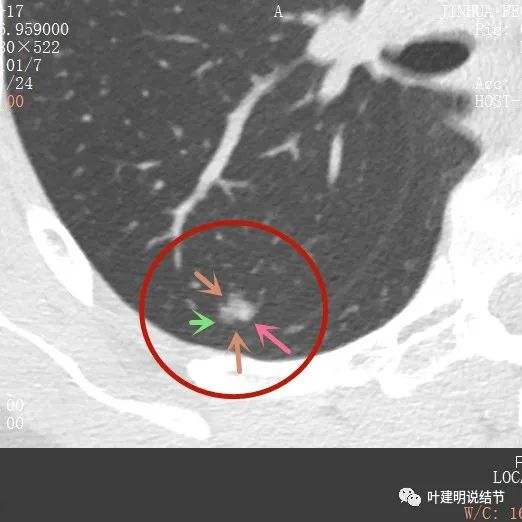

那麼進一步靶掃描這3處結節的細節又是如何的呢?

主病灶此層是磨玻璃,但有明顯血管進入病灶(桔色箭頭)

病灶表現不平,密度雜亂,輪廓相對清楚

有明顯的分葉徵(磚色箭頭)以及磨玻璃成分(綠色箭頭)和偏實性的成分(粉紅色箭頭)

上圖也示病灶有明顯的分葉徵(磚色箭頭)以及磨玻璃成分(綠色箭頭)和偏實性的成分(粉紅色箭頭)

影象後處理與重建的影象顯示了更清楚的資訊,顯示主病灶(下稱A病灶)分葉(磚色箭頭)、有磨玻璃成分(綠色箭頭)以及實性成分(粉紅色箭頭)

病灶鄰近胸膜,密度雜亂

病灶實性佔比較多,輪廓清楚,胸膜有牽拉(藍色箭頭)

綜上所述,病軒A風險程度高,基本上應該是浸潤性腺癌,因為這麼小,是混合磨玻璃,且實性成分佔比較高,所以可能是至少腺泡型為主(也可能含更高風險亞型)伴貼壁成分(因為有磨玻璃成分,雖佔比少);B病灶考慮不典型增生可能性大,不能排除原位腺癌,若沒有A在,它可安全隨訪;C病灶考慮至少原位腺癌,也可能是微浸潤性腺癌,因為密度較高。若病為A在,它也因為過小,可隨訪。好在三個病灶都在上葉後段,那麼如果做上葉後段切除能一次解決目前所有病灶。所以我是建議其儘早手術的。今天要分享這個病例的目的還不是在這,而是我們再來看她2年前的片子,看病灶情況的演變,帶給我們的思考。先看其2年前的片子: